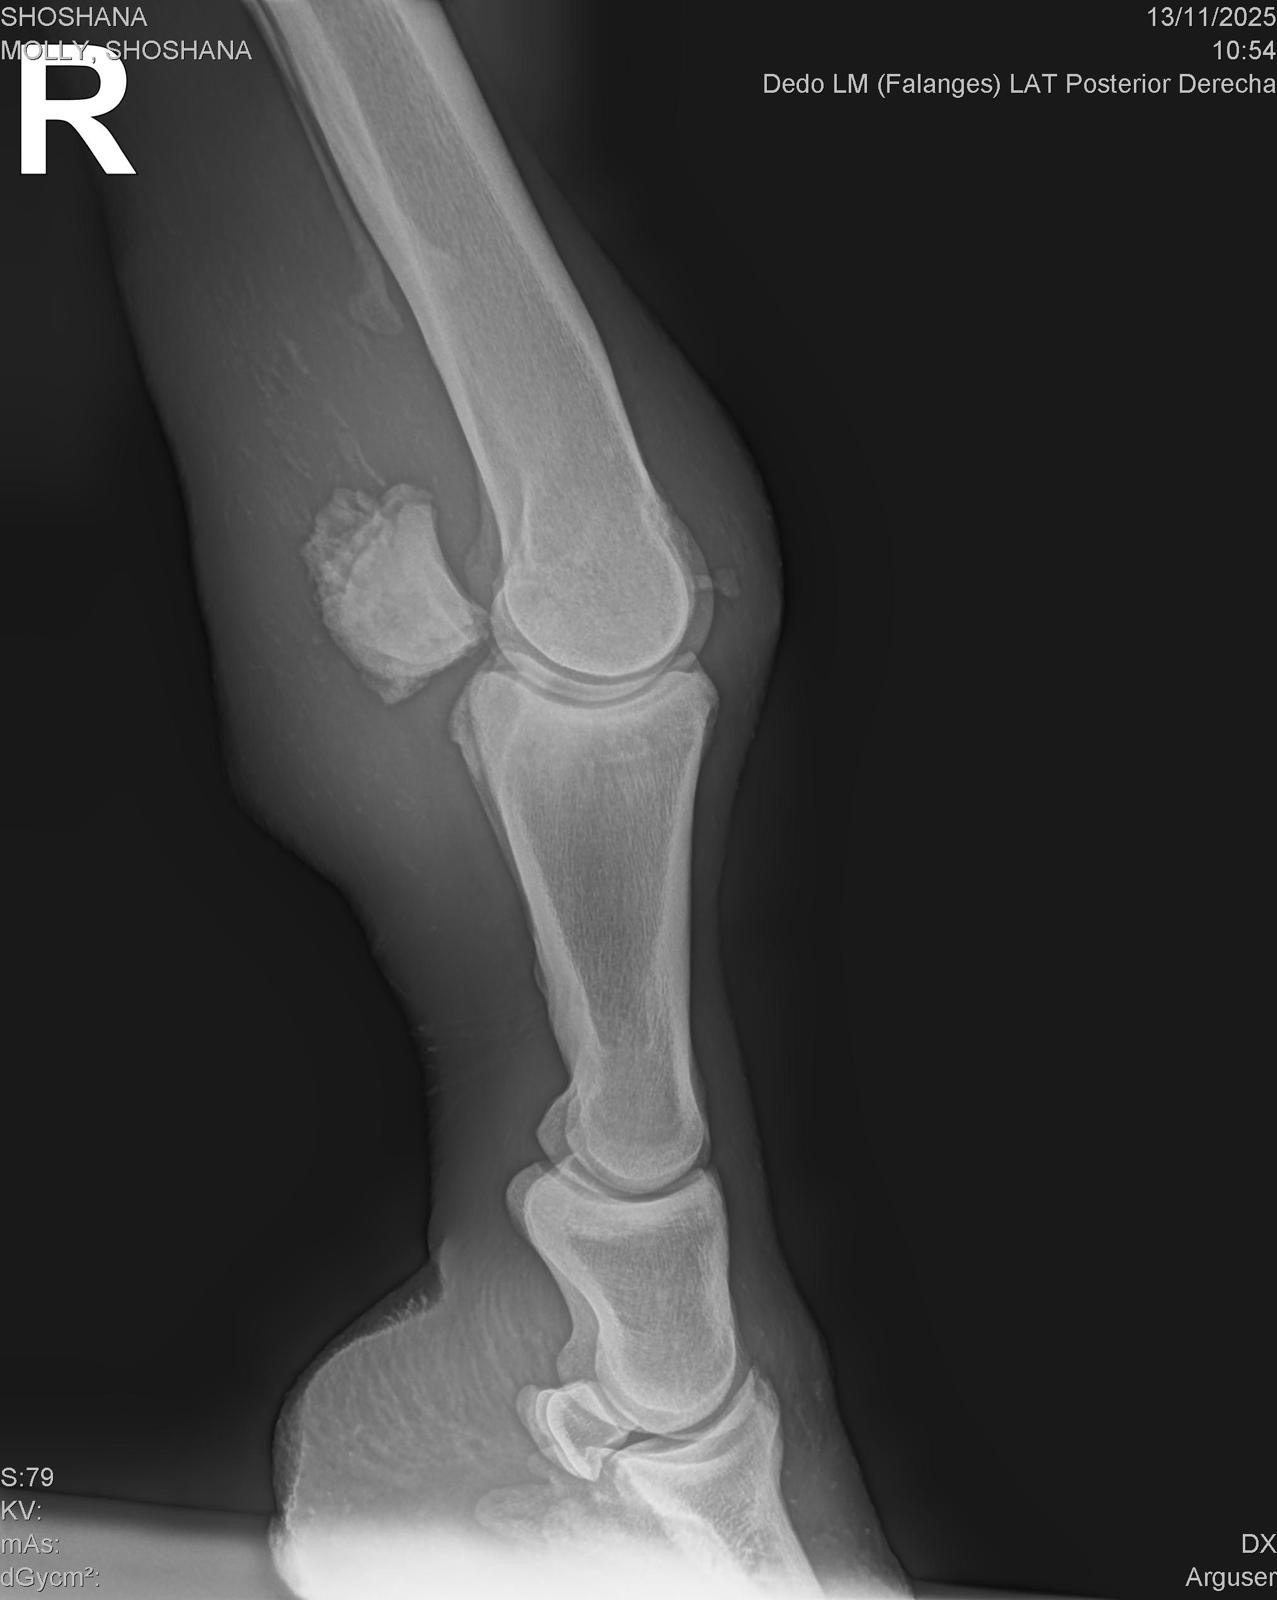

As she began her recovery, the reason for her abandonment slowly became clear. Shoshana has equine OCD (osteochondritis dissecans) — a serious yet treatable joint condition that has caused a piece of bone to fragment and float within her joint. This fragment has now caused a painful joint infection, putting her at significant medical risk.

Just a few days ago, Shoshana suffered a new and serious injury. While running in the field, she likely slipped, tearing the sesamoid ligaments at the back of her hock. This has caused the sesamoid bone to become displaced, adding severe pain and instability to an already fragile situation.

• Her OCD is chronic and will require surgery to resolve it

• The torn ligaments and displaced sesamoid bone also require surgical intervention